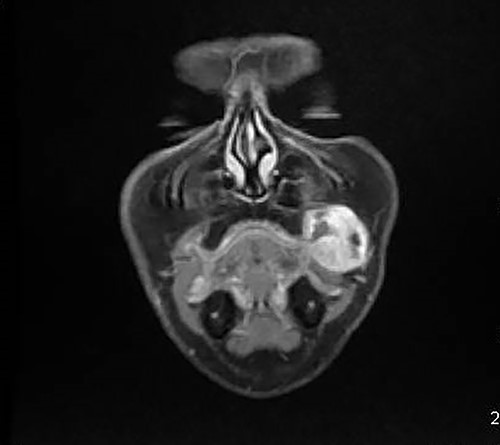

A 46-year-old woman, without clinical antecedent, presented with a tumor in the inner side of the left cheek which had rapidly grown for 3 weeks. Physical examination revealed an ulcerating mass measuring 4 × 3.5 cm, well-circumscribed, fleshly, with a white surface. There was submandibular lymphadenopathy, ranging in dimension from 1 to 1.5 cm in diameter. Magnetic resonance imaging (MRI) scan revealed the tumor of the cheek without mandibular bone infiltration or sinonasal involvement (Fig. 1). Chest computed tomography and abdominal ultrasound scan were unremarkable. An excisional biopsy was performed. Pathological examination showed a neoplastic proliferation composed of mixture of mature benign epithelial components, such as intestinal type, respiratory and squamous epithelia, and mature mesenchymal components, such as muscular tissue and cartilage (Fig. 2) and neuroglial tissue. In addition, immature and malignant tumor components were found such as small blue tumor cells resembling primitive neuroectodermal tumor (Fig. 3), adenocarcinoma and sarcoma with muscular and cartilaginous differentiation (Fig. 4). This tumor infiltrates the skeletal muscle with free margins. Immunohistochemically, epithelial components were positive for pankeratin; mesenchymal components showed desmin, myogenin and S-100 positivity and the primitive neuroectodermal tumor component was positive for NSE, CD99, GFAP, synaptophysin and focally for chromogranin. SALL4 was negative. The resected submandibular lymph nodes were devoid of malignant infiltrate. The diagnosis of TCS was established and the patient was treated by combined chemotherapy (cisplatine +5 fluorouracil) and radiation therapy. No recurrence was noted 6 months after treatment.

MRI showing the tumor of the left cheek with contrast enhanced.